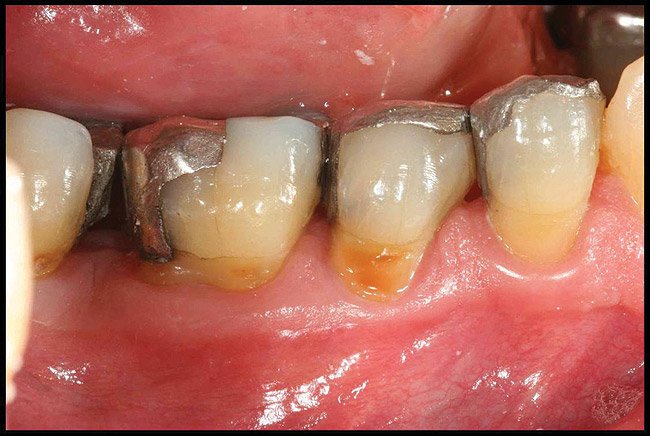

Figureb 2  (A) Clinical and (B) radiographic views of implants at site Nos. 30 and 31 demonstrating bone loss caused by peri-implantitis after 8 years in function. Note gingival inflammation and plaque accumulation around implants.